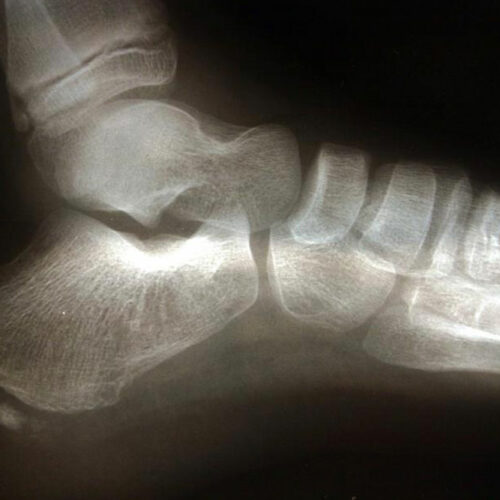

The pain that is experienced by an individual who suffers from osteoarthritis is inexplicable. The chronic condition is caused by friction in the joints of the bone. The ends of the bones are coated with a substance that is known as cartilage. However, when the cartilage breaks down, the ends of the bones are left bare and these lead to soreness and inflammation that increases with each passing day.